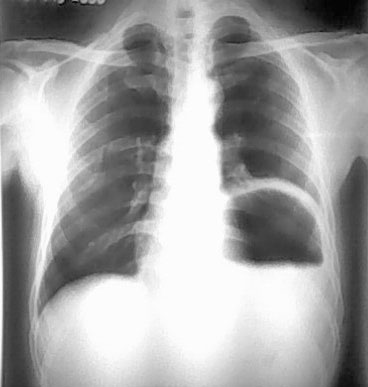

男.55.咳嗽数天

左侧膈肌抬高,其胸腔可见胃泡影,提示膈疝,建议钡餐或ct检查。

壁厚,应该是胃底+膈;有宽大液平面,无肠皱壁,应该是胃腔而不是膈疝或结肠间位;支持膈膨升。

膈膨升与膈疝是两回事,应进一步检查。

膈疝膈肌位置不上升,胃肠位置上移进入胸腔,膈肌动度正常或受限。

膈膨升膈肌位置显著上升,膈肌动度减弱、消失或出现矛盾运动,胃肠位置位于膈下。另外膈麻痹病人膈肌位置也有上升。应注意鉴别。

考虑左侧膈膨升,膈疝待排。